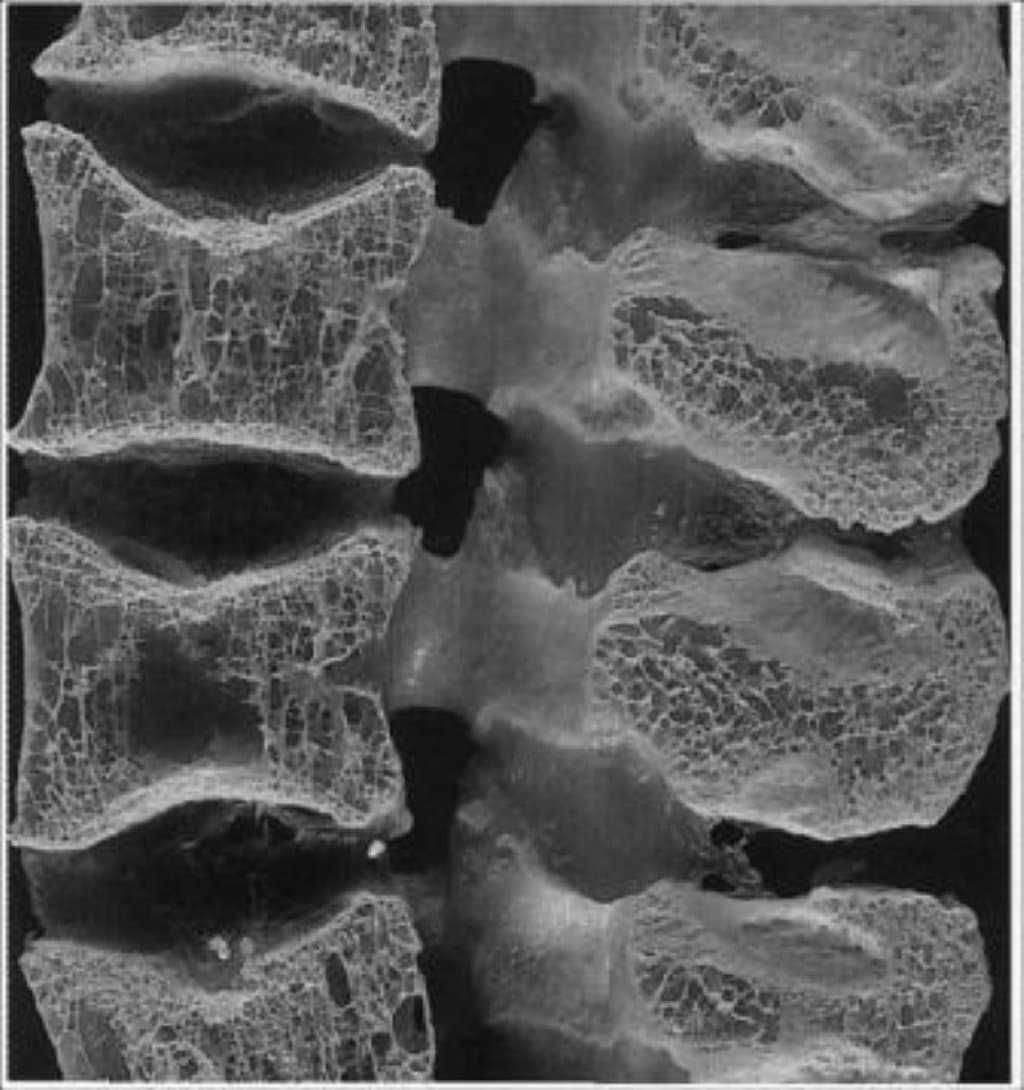

osteoporoz

Osteoporozun ən müəyyən təşhis metodu densitometriya adlanır. Bu, xəstənin sümük dansitəsini ölçmək üçün istifadə olunur. Osteoporozu idarə etmək və ya ləğvetmək üçün müxtəlif yollar mövcuddur. Bunlar arasında düzgün qidalanma (kalsium və D vitamini açısından zəngin qidalanma), fiziki fəaliyyətlərin tənzimlənməsi, kalsium və D vitamini əlavələri, hətta tibbi dərmanlar da olur.